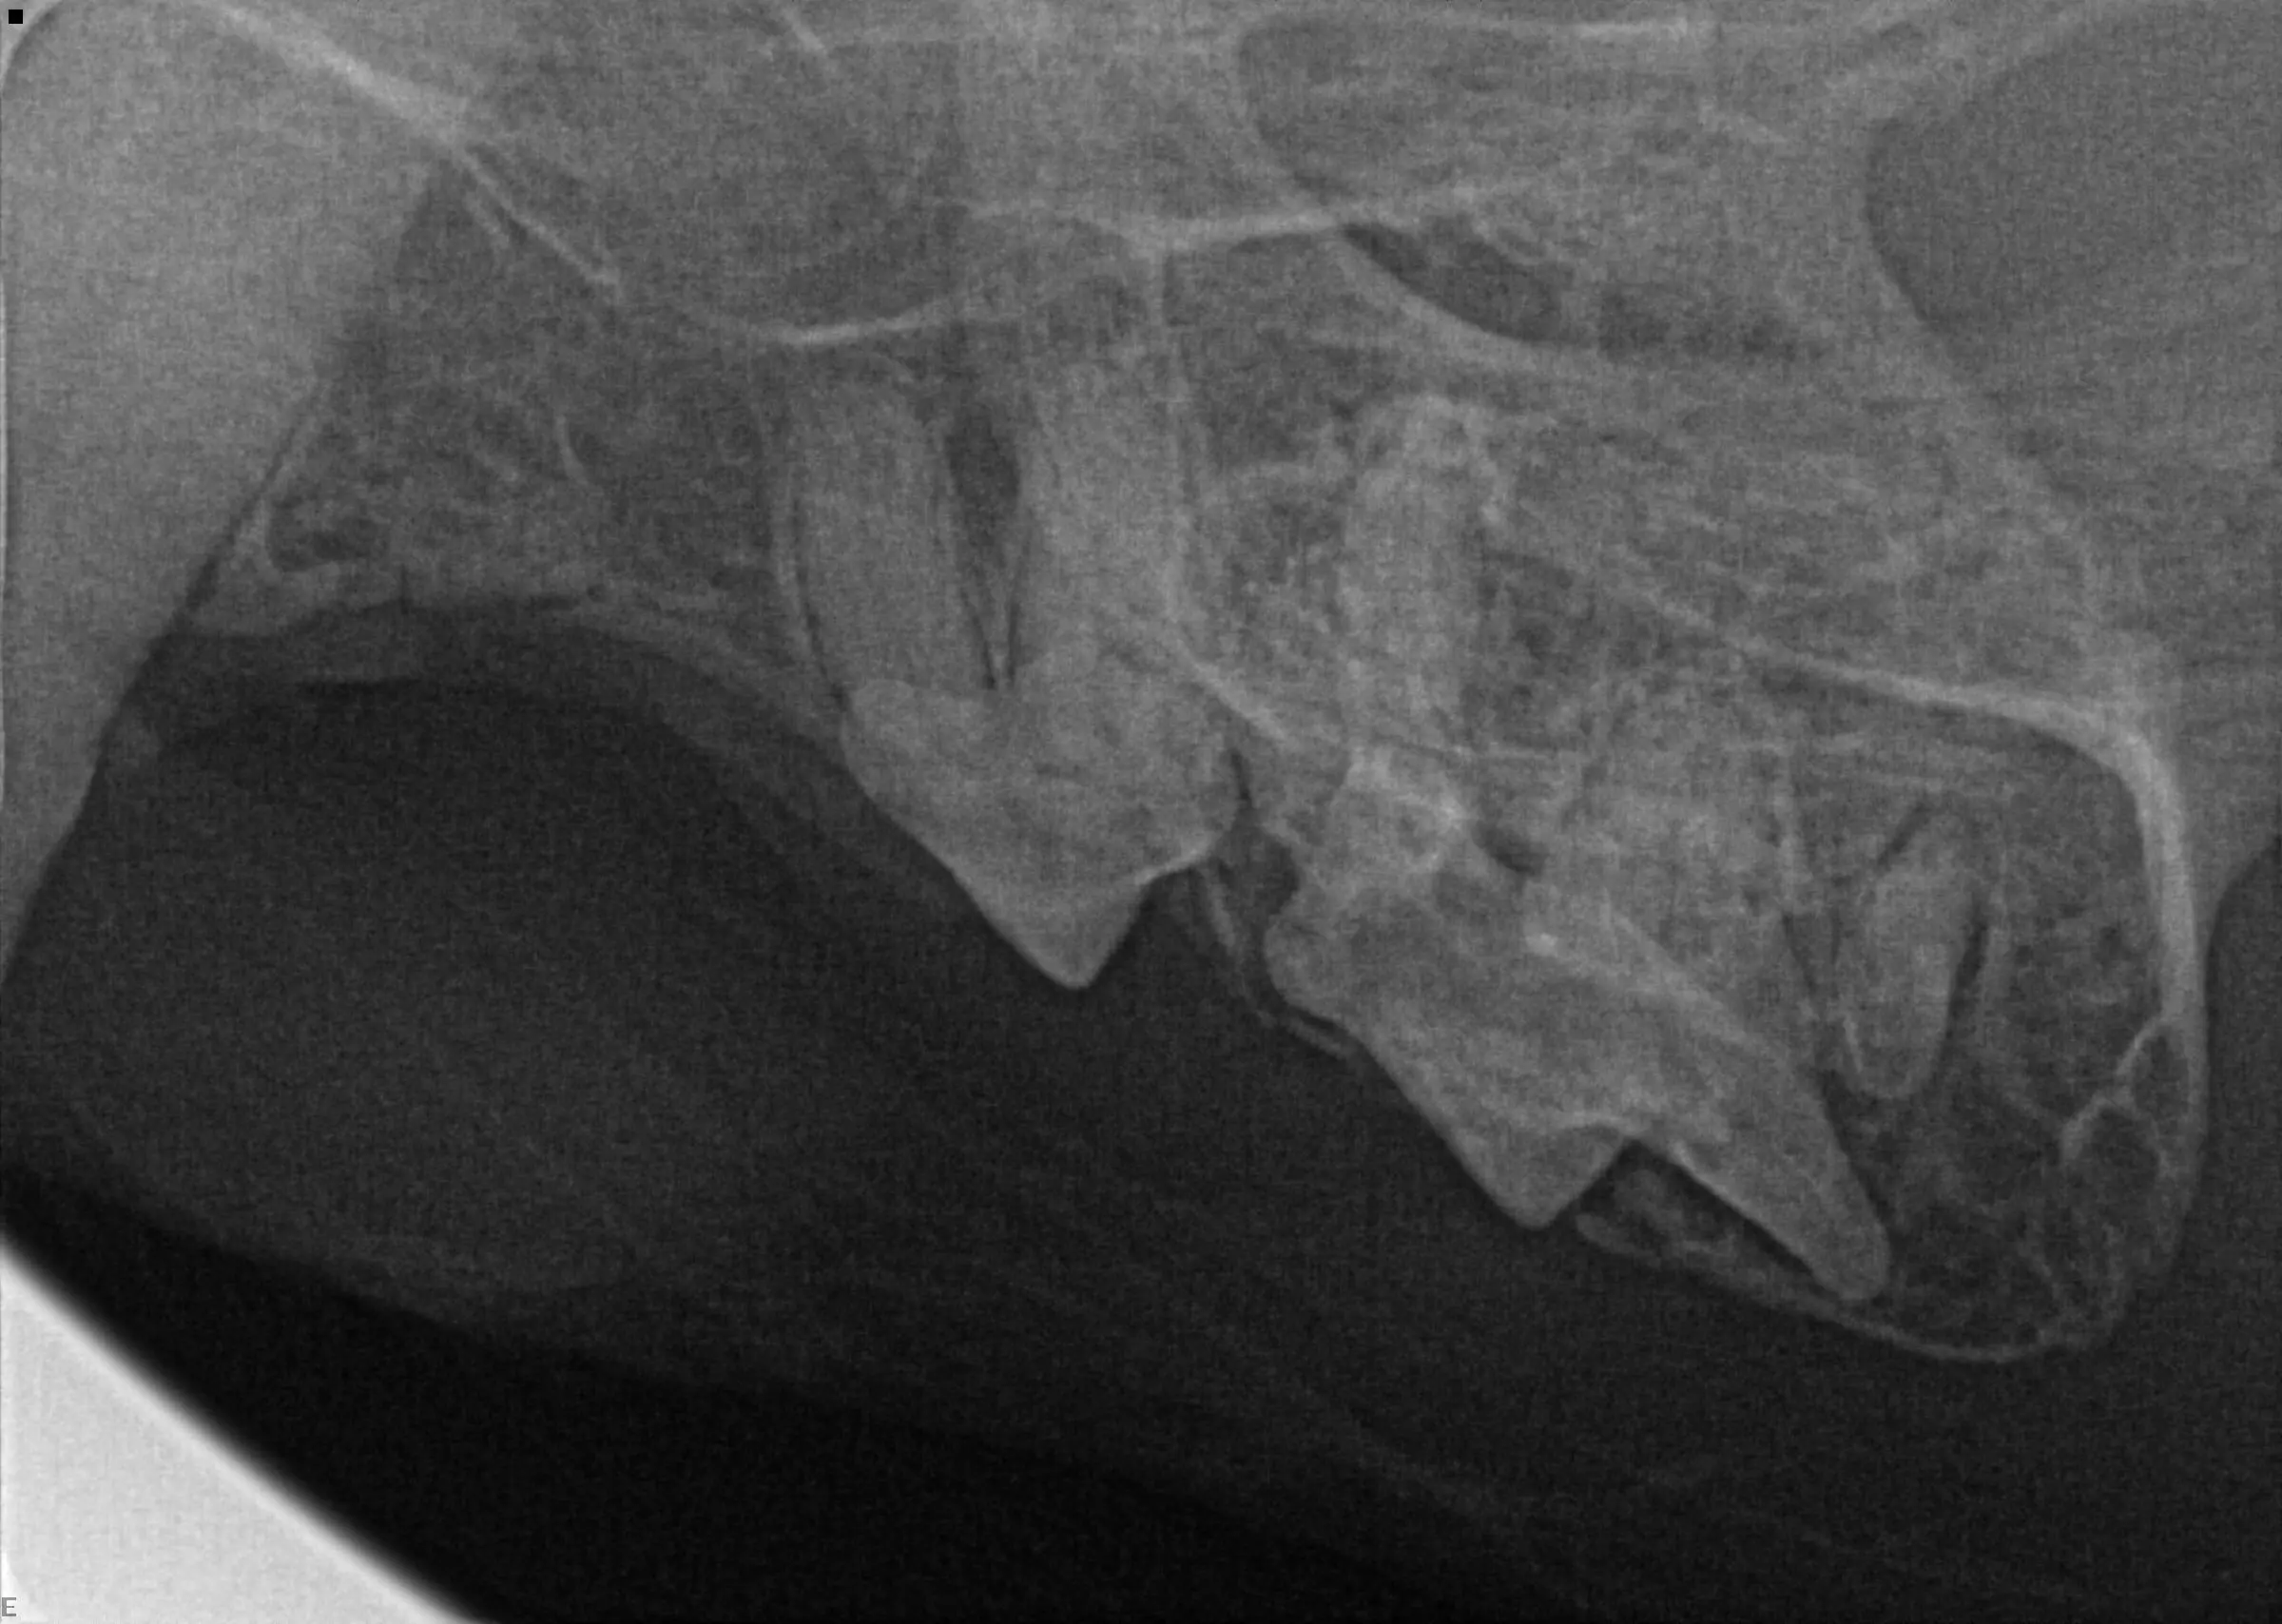

Diagnostic radiographs were taken (see below). What do you see?

There is bone proliferation/expansion in the 208/209 area. Visible tooth resorption (type I) is noted on 208.